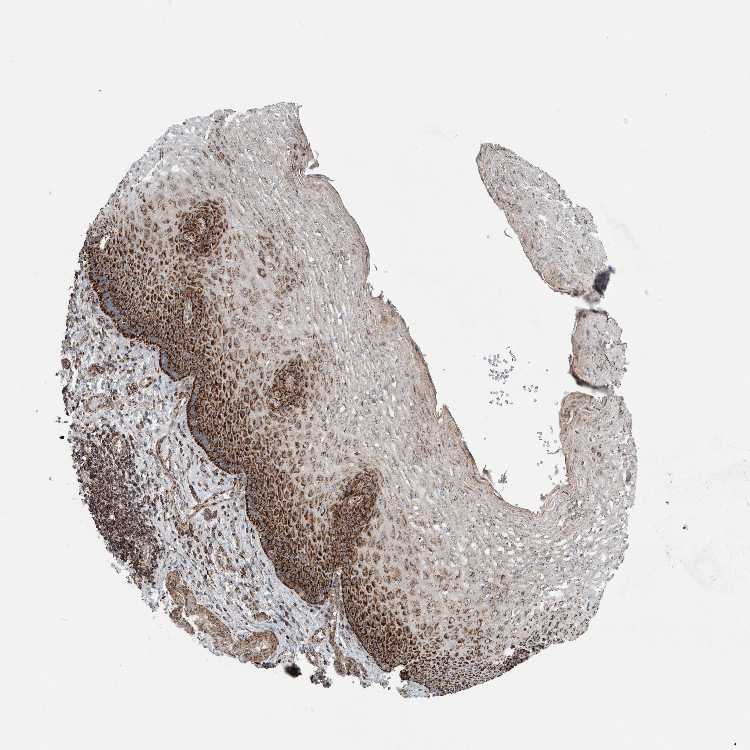

ESOPHAGUS - Antibody stainingi

Antibody staining in the annotated cell types in the current human tissue is reported as not detected, low, medium, or high, based on conventional immunohistochemistry profiling in selected tissues. This score is based on the combination of the staining intensity and fraction of stained cells.

Each image is clickable and will lead to virtual microscopy that enables deeper exploration of all samples and also displays staining intensity scores, fraction scores and subcellular localization as well as patient and tissue information for each sample.

Antibody HPA023319Antibody HPA023320Antibody HPA023321Antibody HPA023325

Squamous epithelial cells HighMediumHighHigh